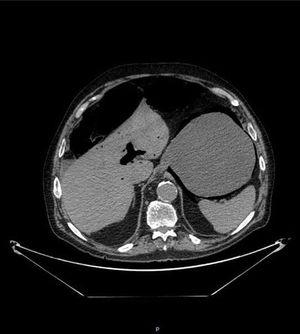

An 82-year-old man presented with bloating and generalized abdominal pain, accompanied by vomiting (dark in color, with an aspect of retention vomiting) and diarrheic stools. A plain abdominal x-ray (Fig. 1) showed air in the gastric wall and bowel segment dilation. An abdominal computed tomography (CT) scan was ordered (Fig. 2) that revealed intramural gas associated with gastric dilation, pneumoperitoneum (Fig. 3), and gas in the portal vein (Fig. 4). An exploratory laparotomy was performed, finding a distended stomach with gas bubbles in its serosa and no signs of transmural necrosis or perforation. Intraoperative gastroscopy identified ulcerated-necrotic mucosa with no spontaneous bleeding on the posterior surface, body, and greater curvature. Given those findings, no further surgical act was carried out. Lactobacillus jensenii was isolated in blood cultures and treated with meropenem + linezolid. The patient progressed favorably, with improvement in the control abdominal CT scan, and was released from the hospital. Emphysematous gastritis is a rare pathology produced by the translocation of gas-producing microorganisms in the walls of the stomach. The causal agent cannot be isolated in up to 42.4%1 of cases and there is a 60% mortality rate.2 CT is the diagnostic study of choice and is essential for making early diagnosis and implementing the vital support treatment with broad-spectrum antibiotics. Surgery is only required if there is no response to conservative treatment or in cases of severe sepsis or gastric perforation.3